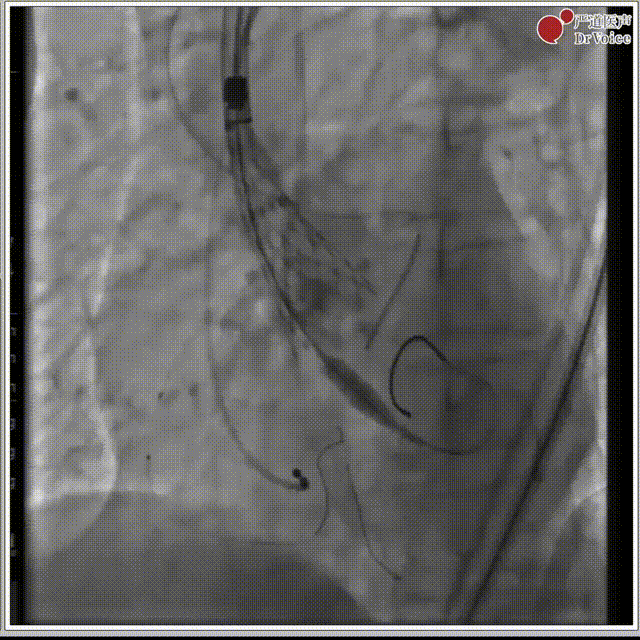

1. 冠脉造影。

冠脉造影图片1

冠脉造影图片2